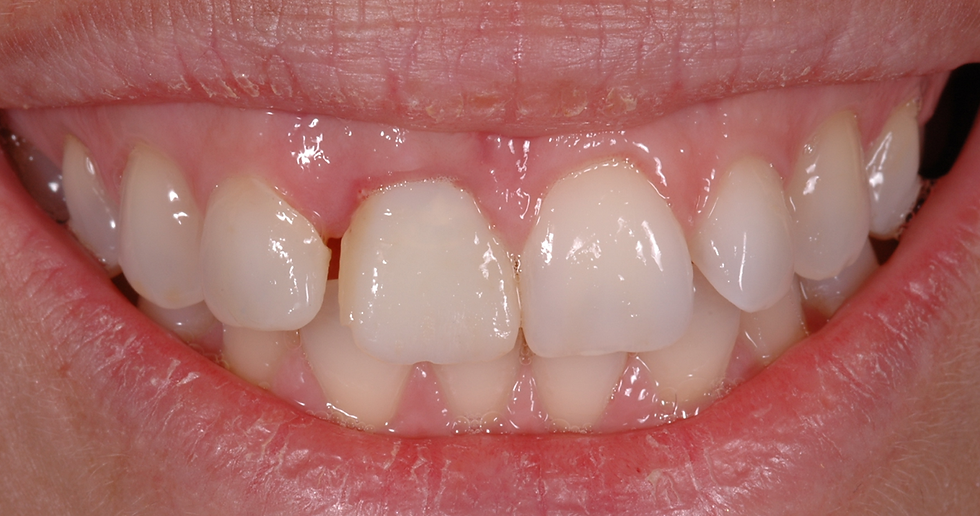

Pre-op clinical image

Detail of pre-op clinical image